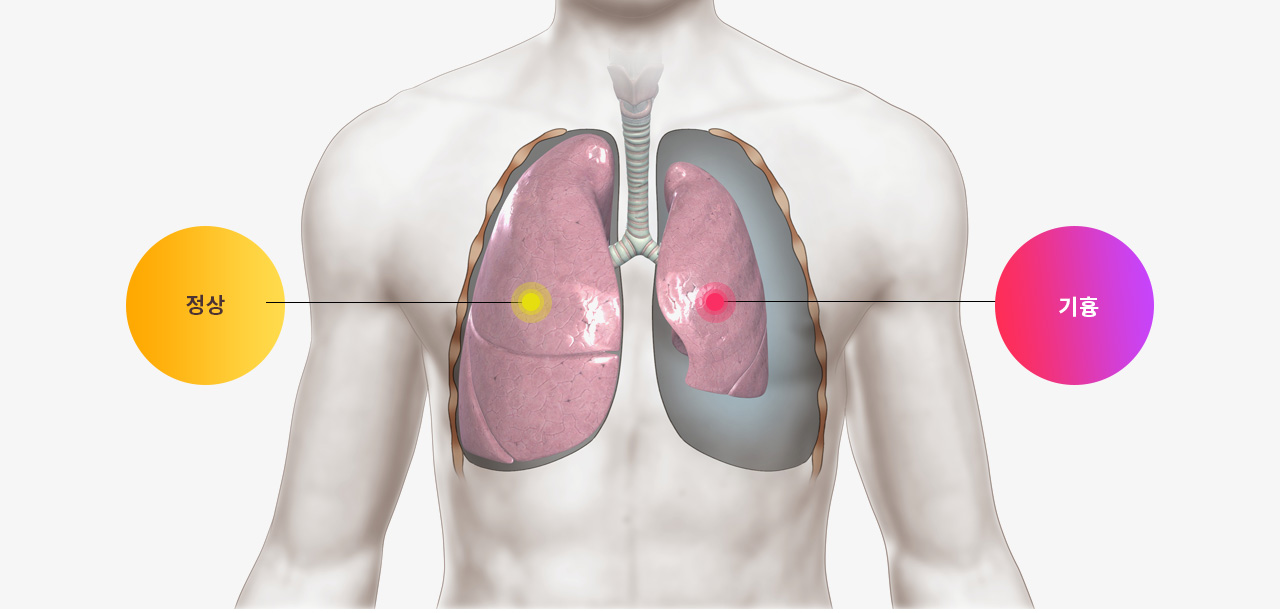

기흉

따라서 반복 재발되는 기흉 치료에 있어서 한의사의 경험과 실력은 매우 중요합니다.